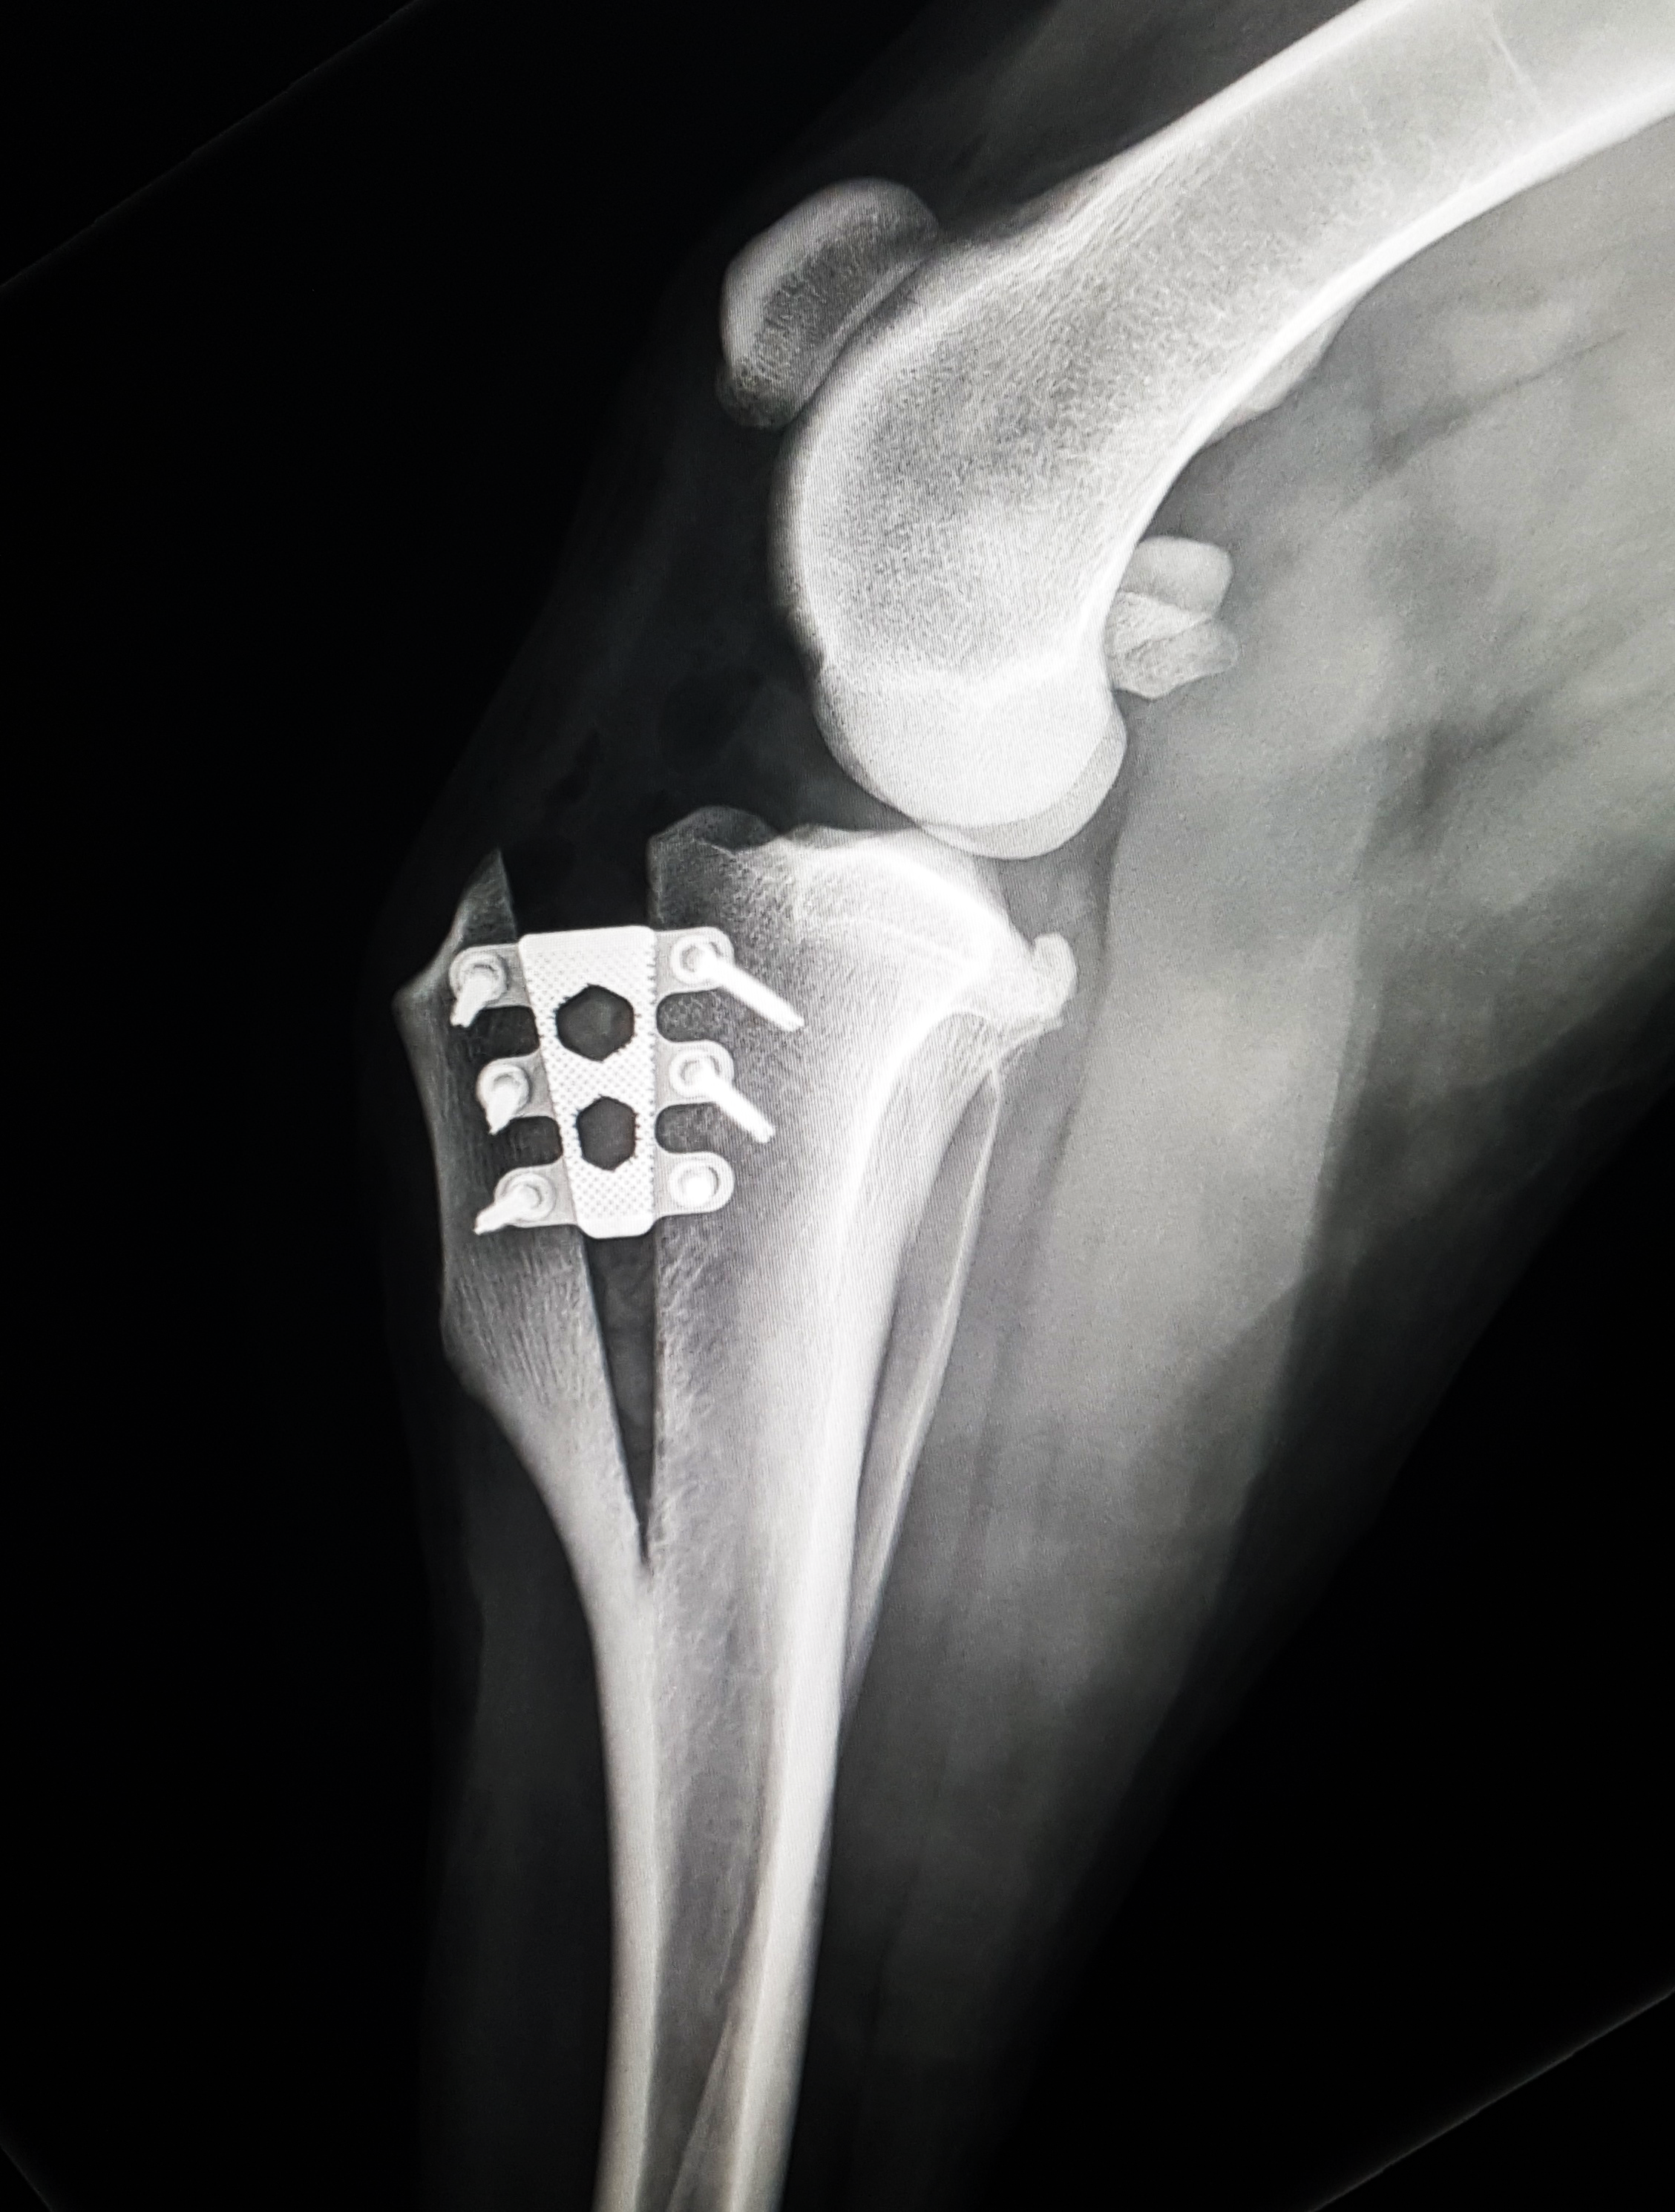

- TTA RAPID Technique: Learn the principles and steps involved in the TTA RAPID® technique, a minimally invasive approach to addressing CCL ruptures. This includes planning the surgery, making precise bone cuts, and utilizing pre-assembled implants for stabilization.

- RAPID Luxation Technique: The course covers the RAPID Luxation Technique, focusing on the addition of a patella luxation spacer to the TTA RAPID Cage. This addresses cases where both CCL injury and patella luxation are present, offering a comprehensive treatment solution.